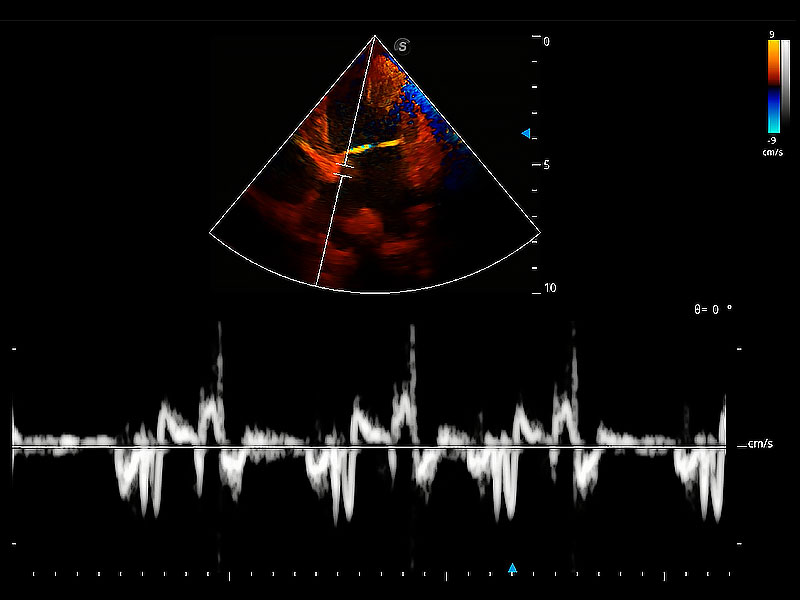

實(shí)時用顏色表示心肌組織運(yùn)動,觀察和定量組織的運(yùn)動情況,對快速檢測與評估心肌的灌注和活性、電傳導(dǎo)及心肌收縮和舒張功能等均能提供重要的診斷信息。

通過360度任意調(diào)節(jié)3條M型取樣線,在同一心動周期上觀察心臟不同位置的運(yùn)動曲線,得到準(zhǔn)確的心功能測量數(shù)據(jù),有效評估心肌運(yùn)動及左心室功能。